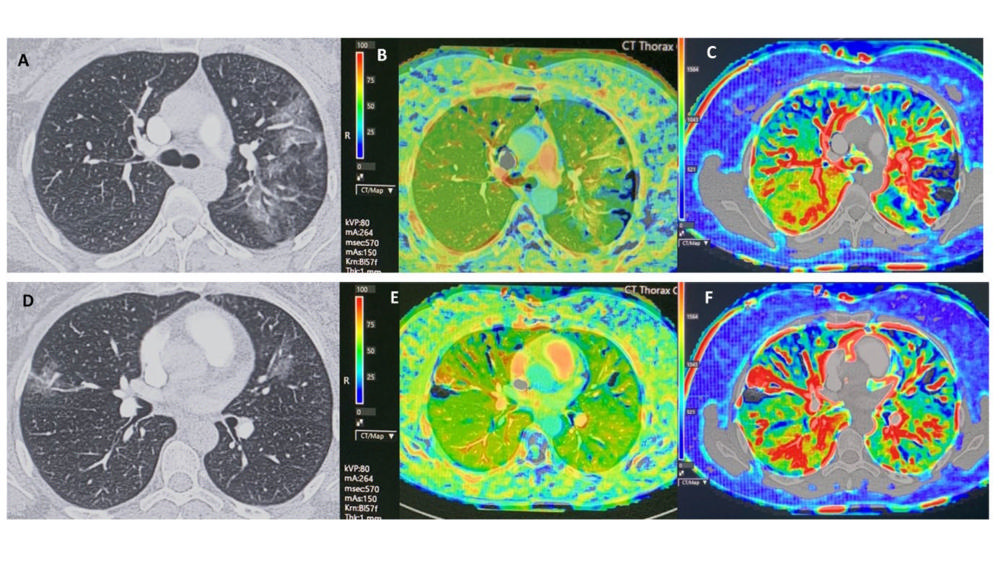

Figure 10. This proof of concept demonstrates CT perfusion findings in phase 1 in a 43-year old female patient proven COVID-19 with multiple ground glass opacities, with plasma D-dimer < 500 ng/ml and without pulmonary embolism on CT pulmonary angiography. There are multiple bilateral perfusion deficits due to microvascular obstruction, with increased blood flow in or adjacent to areas of ground glass opacities. The blood flow is slightly increased in the right lower lobe. Scan parameters: Conventional Dynamic Perfusion CT, Somatom Drive, Siemens; Scan volume 8,4 cm (aorta arch – left atrium); 1 mm recon; Dual input lung perfusion 4D, Vitrea, Vital, Canon; pulmonary flow: ml/min./100 ml; arterial flow: ml/min./100 ml; perfusion Index: % Baseline chest CT findings in selected slices (A, D), with perfusion index (B, E) and pulmonary arterial flow (C, F) in corresponding slices. (Figure courtesy of Department of Radiology, Haaglanden Medical Centre, The Hague, the Netherlands.) (van Beek, et al.)

High-res (TIF) version